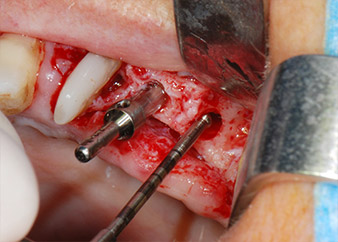

Antes de colocar el implante, el tejido infectado del hueso alveolar ubicado en el lugar del implante y alrededor de los dientes del pilar se retiró con un inserto concebido en un principio para modelar huesos y recoger virutas óseas: Piezomed y el inserto B5 (figuras 6 y 7).

En el siguiente paso, los lechos del implante se prepararon en las posiciones 25 y 26 con instrumentos rotatorios, utilizando un contra-ángulo con un coeficiente de transmisión de 20:1 (WS-75 L, W&H), junto con el nuevo potente motor de implantes Implantmed de W&H (figuras 8 y 19).

La preparación final junto al seno se realizó de nuevo con un inserto piezoeléctrico (Piezomed S2).